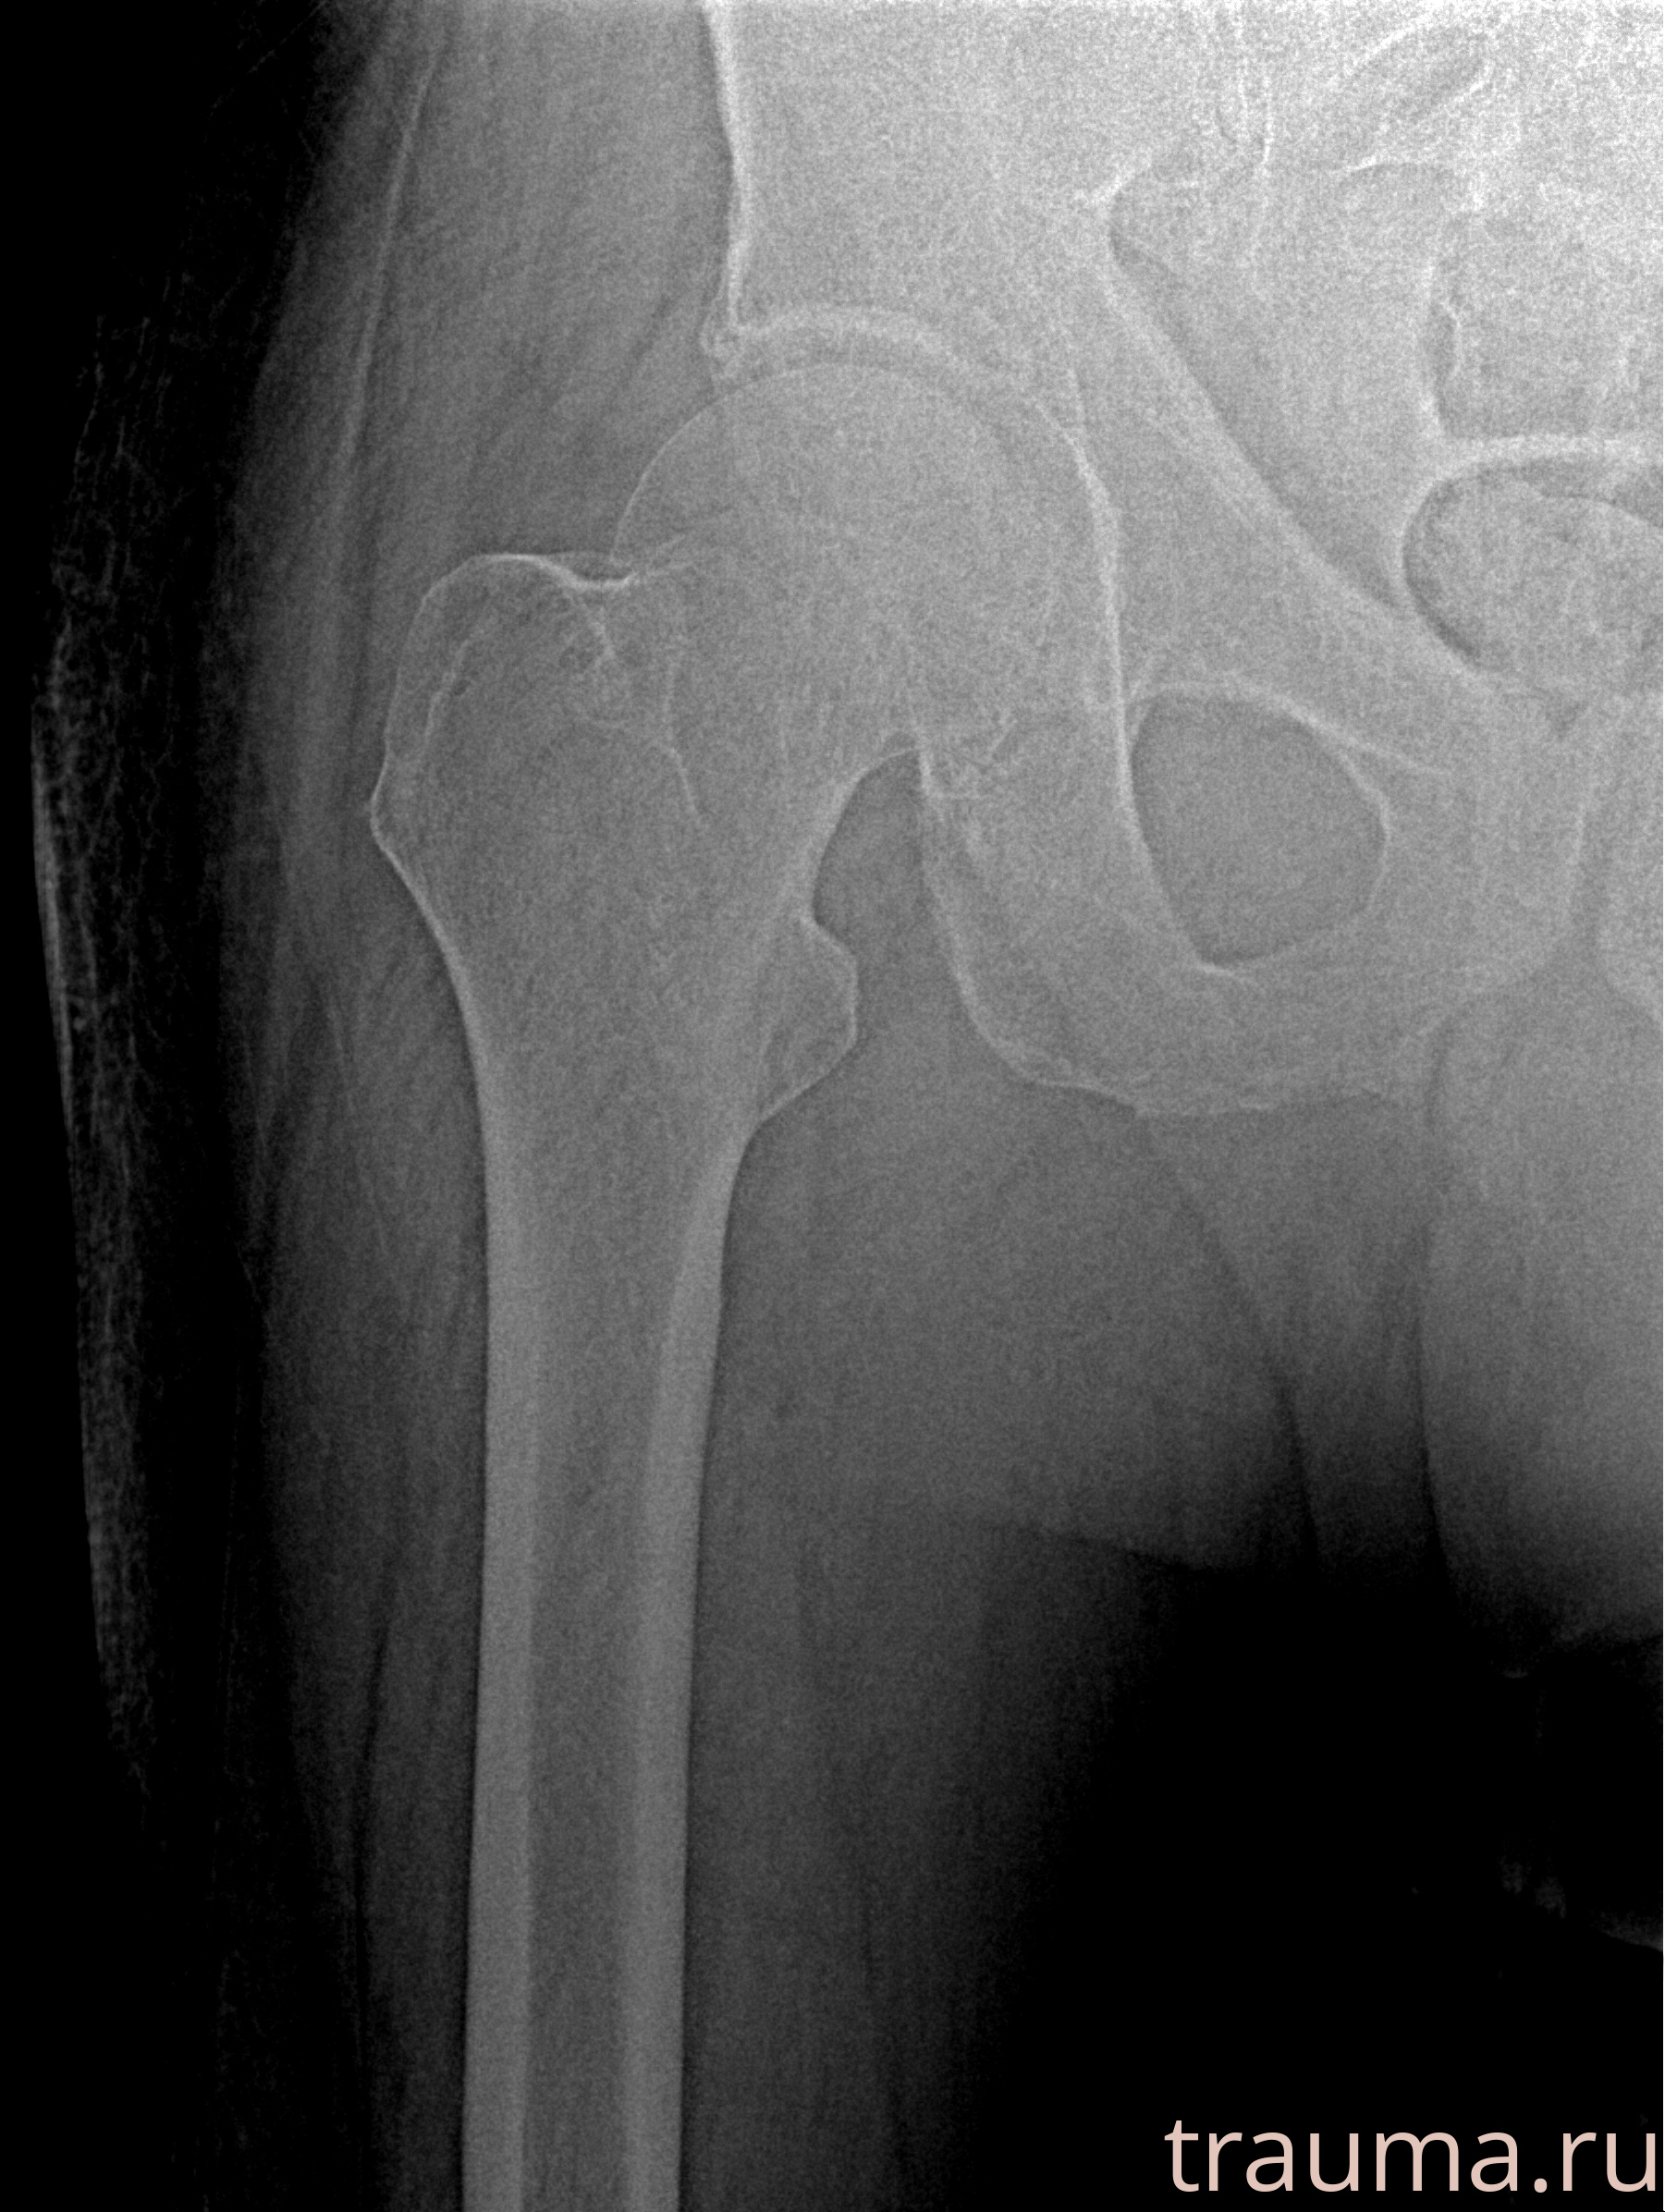

Первая помощь при переломе шейки бедра

Рентген на дому: по вашему адресу приезжает врач-рентгенолог, травматолог-ортопед с мобильным рентгеновским аппаратом, проводит диагностику травмы или заболевания, делает необходимые рентгенограммы, дает рекомендации по дальнейшему лечению. Получить качественные снимки в домашних условиях возможно благодаря уникальной методике, разработанной МосРентген Центром для института  Склифосовского